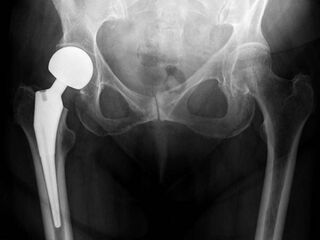

![]() An X-ray showing a left hip (right of image) that has been replaced, with the ball of this ball-and-socket joint replaced by a metal head that is set in the femur and the socket replaced by a cup | |

Post-operative projectional radiography is routinely performed to ensure proper configuration of hip prostheses.